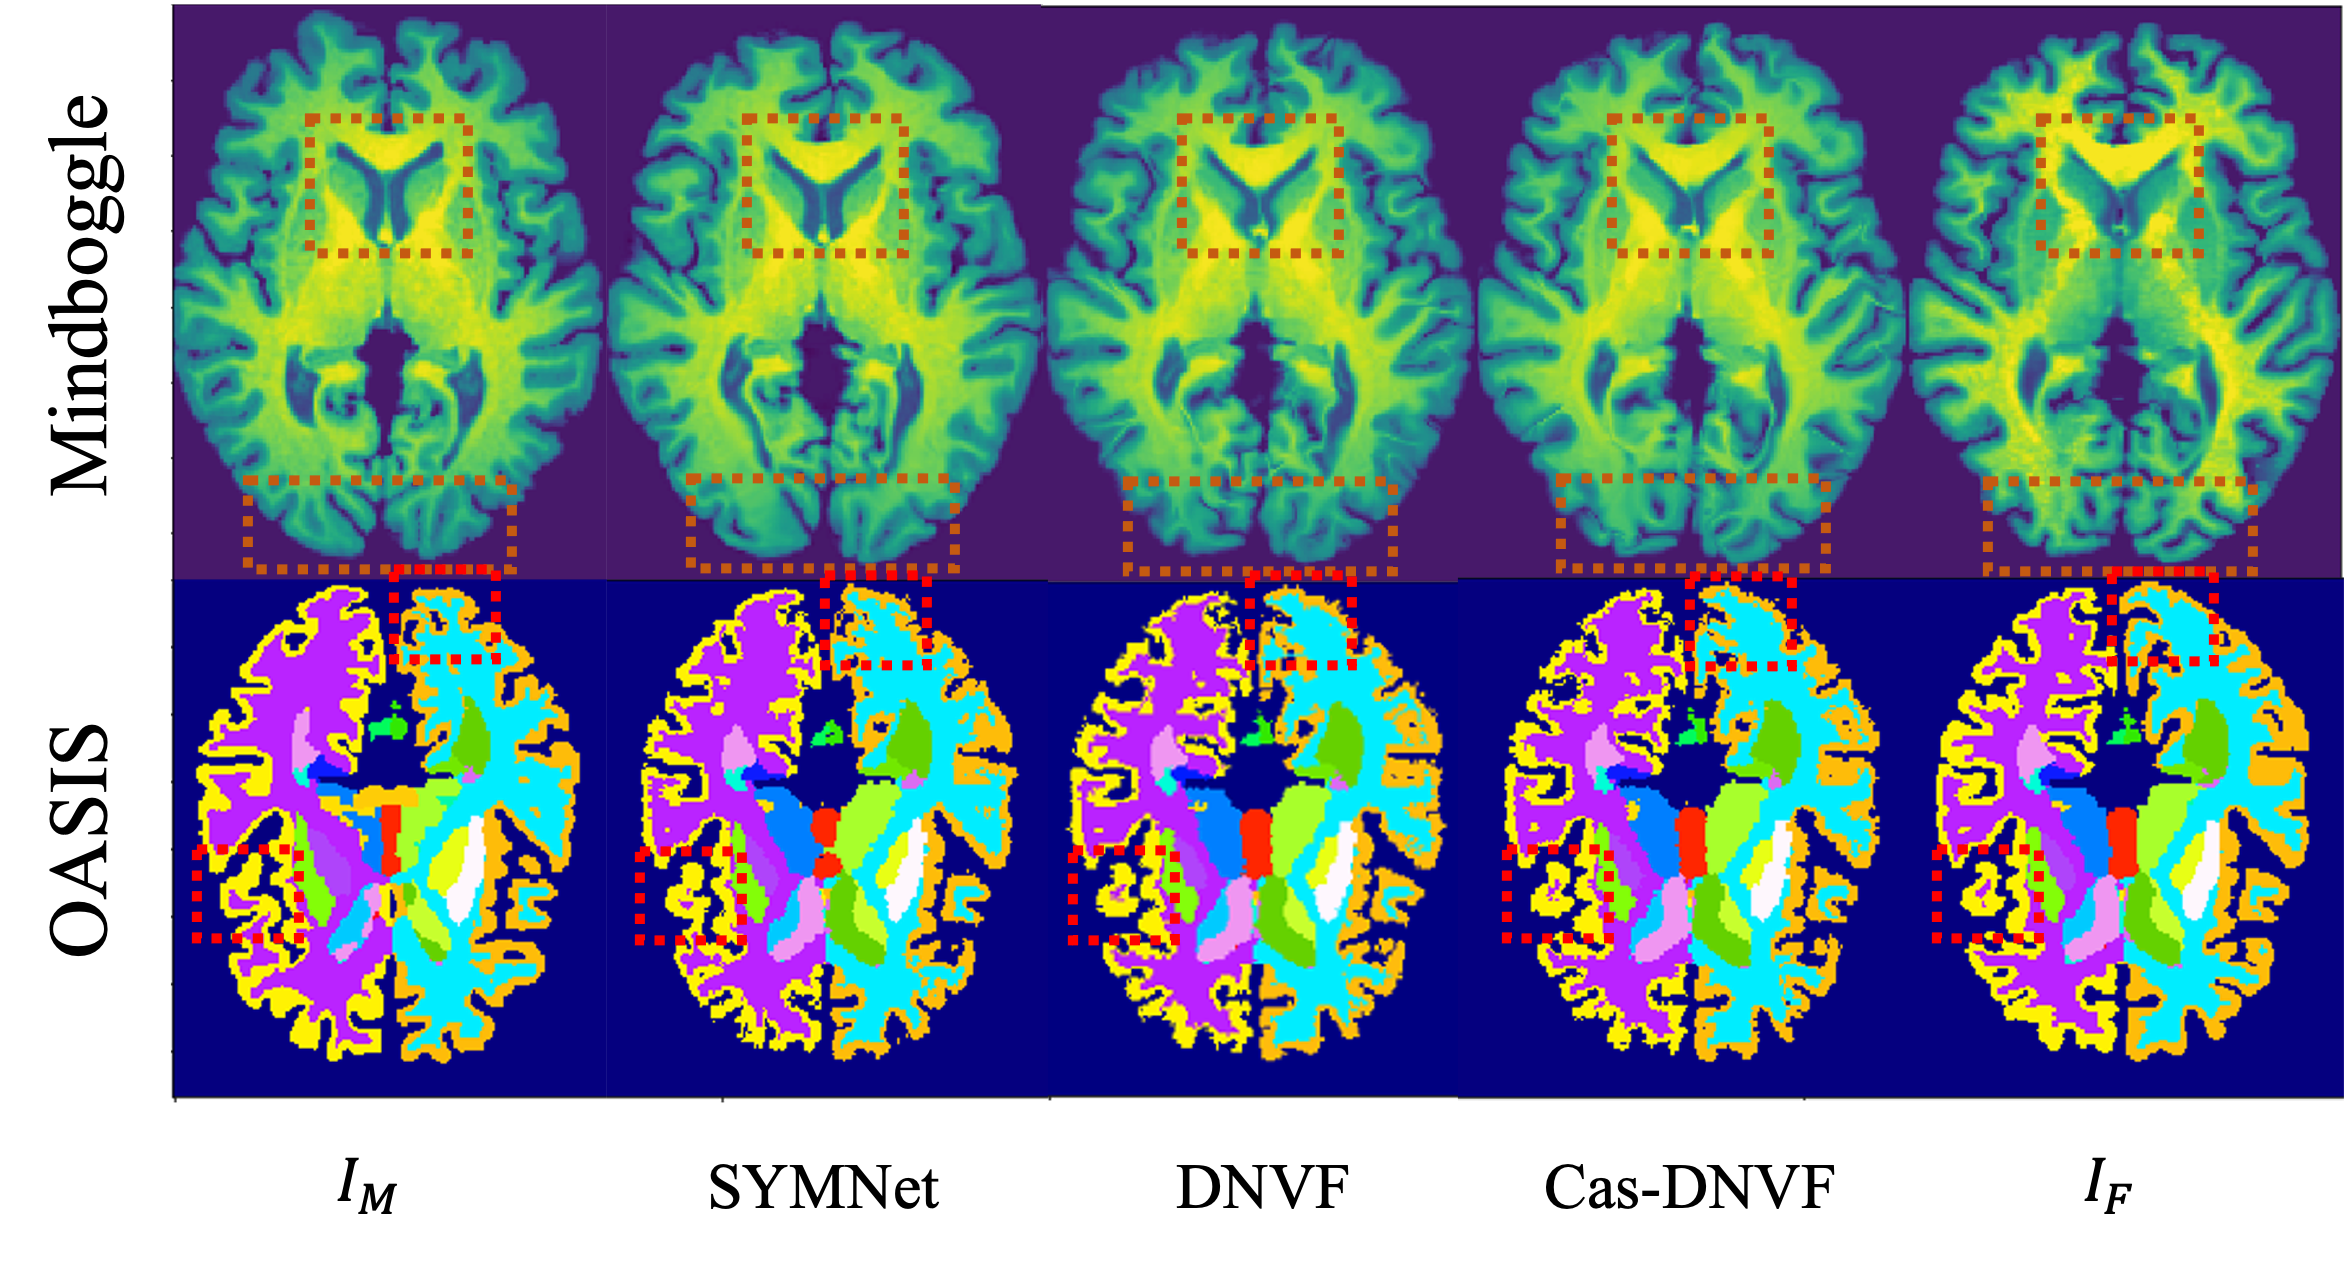

Visualization

Figure 3 shows some visualization of registration results. Current SOTA method provides a reasonable matching between pair of images, however, some local small deformations are missing in both cortical and subcortical regions. Benefiting from the our neural velocity field representation, DNVF and Cas-DNVF are able to capture the local small deformations with better capability in fitting high-frequency content.

Refer to caption

Figure 3: Visualization of registration results. First row compares the warped images from Mindboggle dataset and the second row shows the anatomical structures after the registration for OASIS dataset.